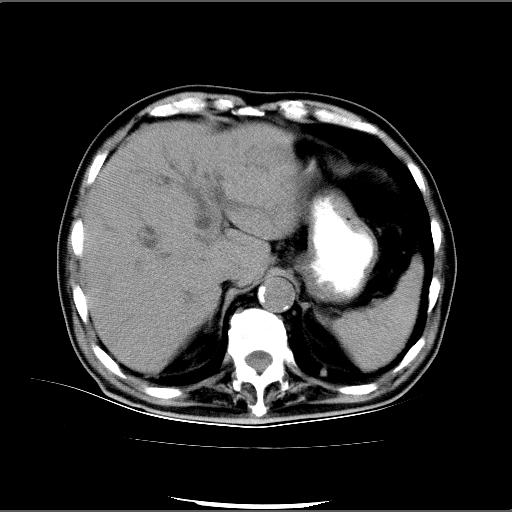

患者男82岁,黄染,发热10天,无腹痛。

1胆总管下端结石伴肝内外胆管扩张;2胆囊颈部结石伴胆囊积液

胆囊多发结石,胆囊积液;胆总管中下段结石,中上段扩张。

胆总管下段结石伴胆道系统扩张;胆囊炎伴胆囊结石.

1、胆总管壶腹部结石并胆总管、胆囊及肝内胆管扩张。2、胆囊多发结石。3、两下胸膜局限性增厚。4、胃体部大弯侧胃壁稍厚,建议:多量饮水后增强ct扫描除外占位性病变。

此病例有结果了:患者术后为:胆总管下段结石伴胆道系统扩张;胆囊炎伴胆囊结石。

各位战友分析的都很正确,是一个典型的病例。